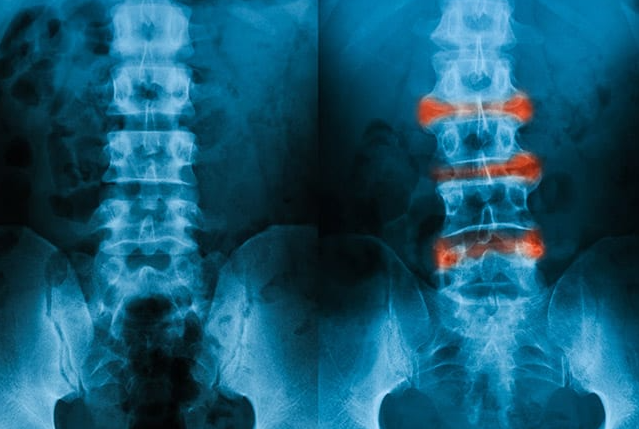

1. 영상 검사 결과

X-ray, MRI 등 영상검사는 척추의 강직 정도나 관절 유합 상태를 파악하는 주요 근거입니다. 척추의 변형, 인대의 석회화, 천장관절 손상 등의 유무가 중요하게 평가됩니다.